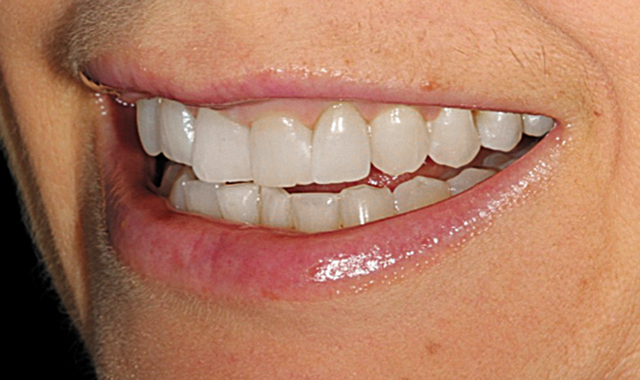

This patient presented with concerns over the esthetics of her smile due to the shifting of her teeth over time (Figs. 1-3). We diagnosed crowding and asymmetry of her teeth and gingival tissues. Our treatment plan included Invisalign treatment, occlusal equilibration after orthodontics and Vivera retainers.

Our Invisalign treatment led to a very successful clinical result. The crowding and the asymmetries of tooth position, arch form and gingival levels were beautifully corrected (Figs. 14-16).